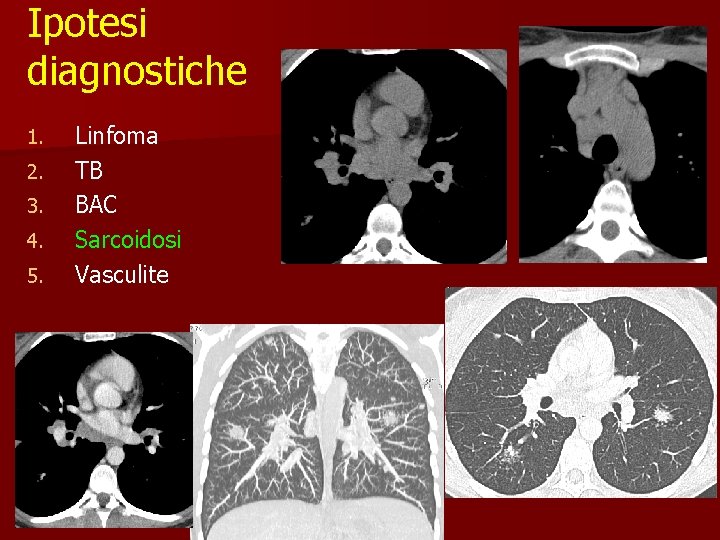

Caso clinico n n n 29 anni Donna Lieve ipertermia Artralgie Non fumatrice Non sintomi respiratori

Ipotesi diagnostiche 1. 2. 3. 4. 5. Linfoma TB BAC Sarcoidosi Vasculite